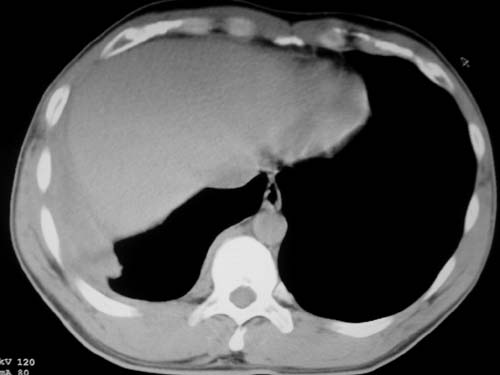

标题: CT19540: 31岁。自述结核性胸水治疗两个月后,在外院拍x线发 [打印本页]

标题: CT19540: 31岁。自述结核性胸水治疗两个月后,在外院拍x线发

右侧胸壁结节状软组织影伴相应肺叶内受侵,伴右侧胸腔积液。考虑:结核性可能大。

1、炎性包块;2、右侧少量胸膜积液。

1、炎性病变,结核可能;2、右侧少量胸膜积液。

病灶也是发生于结核球好发部位,支持结核

考虑结核性结节

多考虑包裹性胸腔识液。

右侧胸壁结节状软组织影伴相应肺叶内受侵,伴右侧胸腔积液,结合临床,首先考虑结核。

考虑结核性胸膜炎,胸膜肥厚,不除外胸膜间皮瘤可能,建议复查。

支持结核,胸膜间皮瘤不排除.

1)考虑右侧结核性胸膜结节。2)右侧胸膜增厚+包裹性胸腔积液。

支持结核性胸膜炎表现

结核性脓胸、肺内结核?